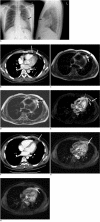

Pericardial fat necrosis is an infrequent cause of acute chest pain and this can mimic acute myocardial infarction and acute pericarditis. We describe here a patient with the magnetic resonance imaging (MRI) findings of pericardial fat necrosis and this was correlated with the computed tomography (CT) findings. The MRI findings may be helpful for distinguishing pericardial fat necrosis from other causes of acute chest pain and from the fat-containing tumors in the cardiophrenic space of the anterior mediastinum.